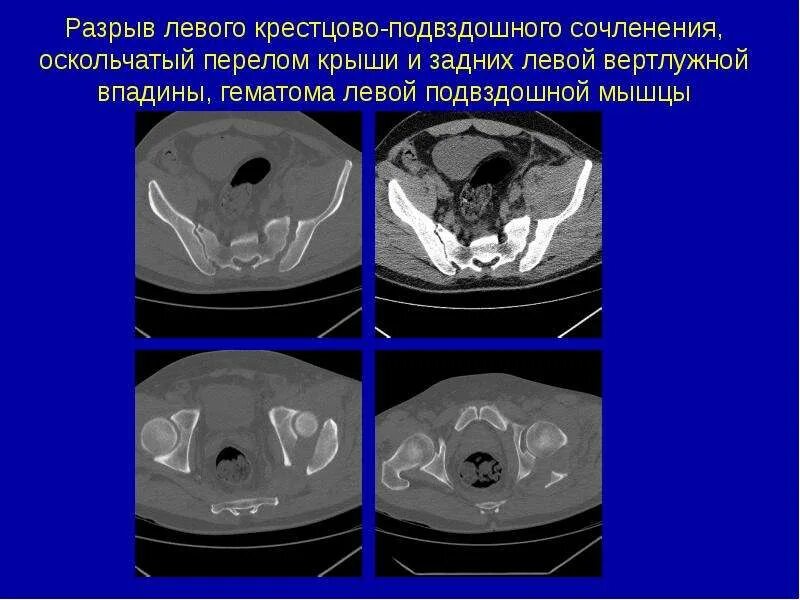

Разрыв крестцово подвздошного сочленения